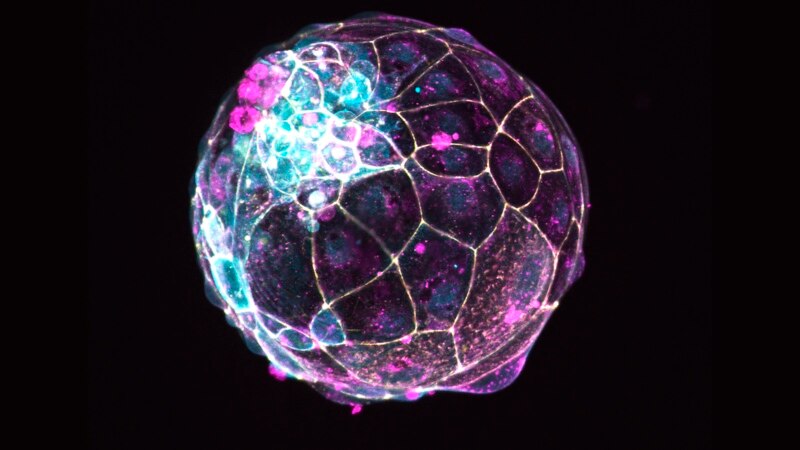

This image, provided by the Institute of Molecular Biology of the Austrian Academy of Sciences, shows a human “blastoid” created in a lab. (Photo by Alok Javali, Heidar Heidari and Theresa Sommer/Institute of Molecular Biology of the Austrian Academy of S

This image, provided by the Institute of Molecular Biology of the Austrian Academy of Sciences, shows a human “blastoid” created in a lab. (Photo by Alok Javali, Heidar Heidari and Theresa Sommer/Institute of Molecular Biology of the Austrian Academy of S